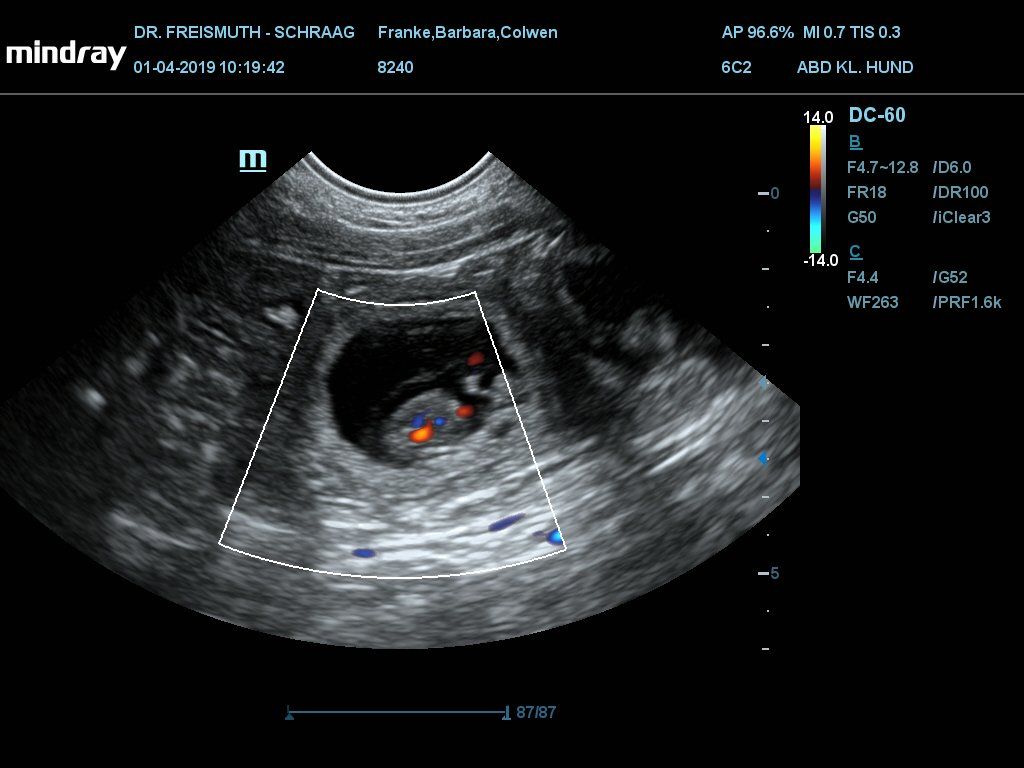

Heute Ultraschalltermin zur Trächtigkeitsbestätigung.

Ich bin doch etwas nervös, vor allem weil bei drei anderen Würfen fast zur gleichen Zeit keine, oder nur sehr wenige Welpen gesehen wurden.

Als ich beim Schallen den ersten Welpen gesehen habe, hatte ich Tränen in den Augen vor Freude. Die Tierärztin hat 5 Welpen gesehen.

Gewicht: 29kg (-200g)